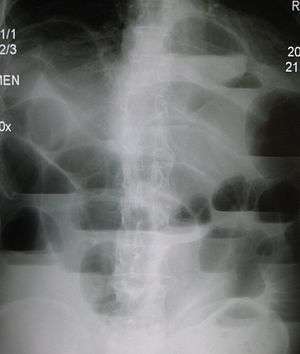

Upright abdominal X-ray of a patient with a large bowel obstruction showing multiple air fluid levels and dilated loops of bowel.

Causes of large bowel obstruction include: